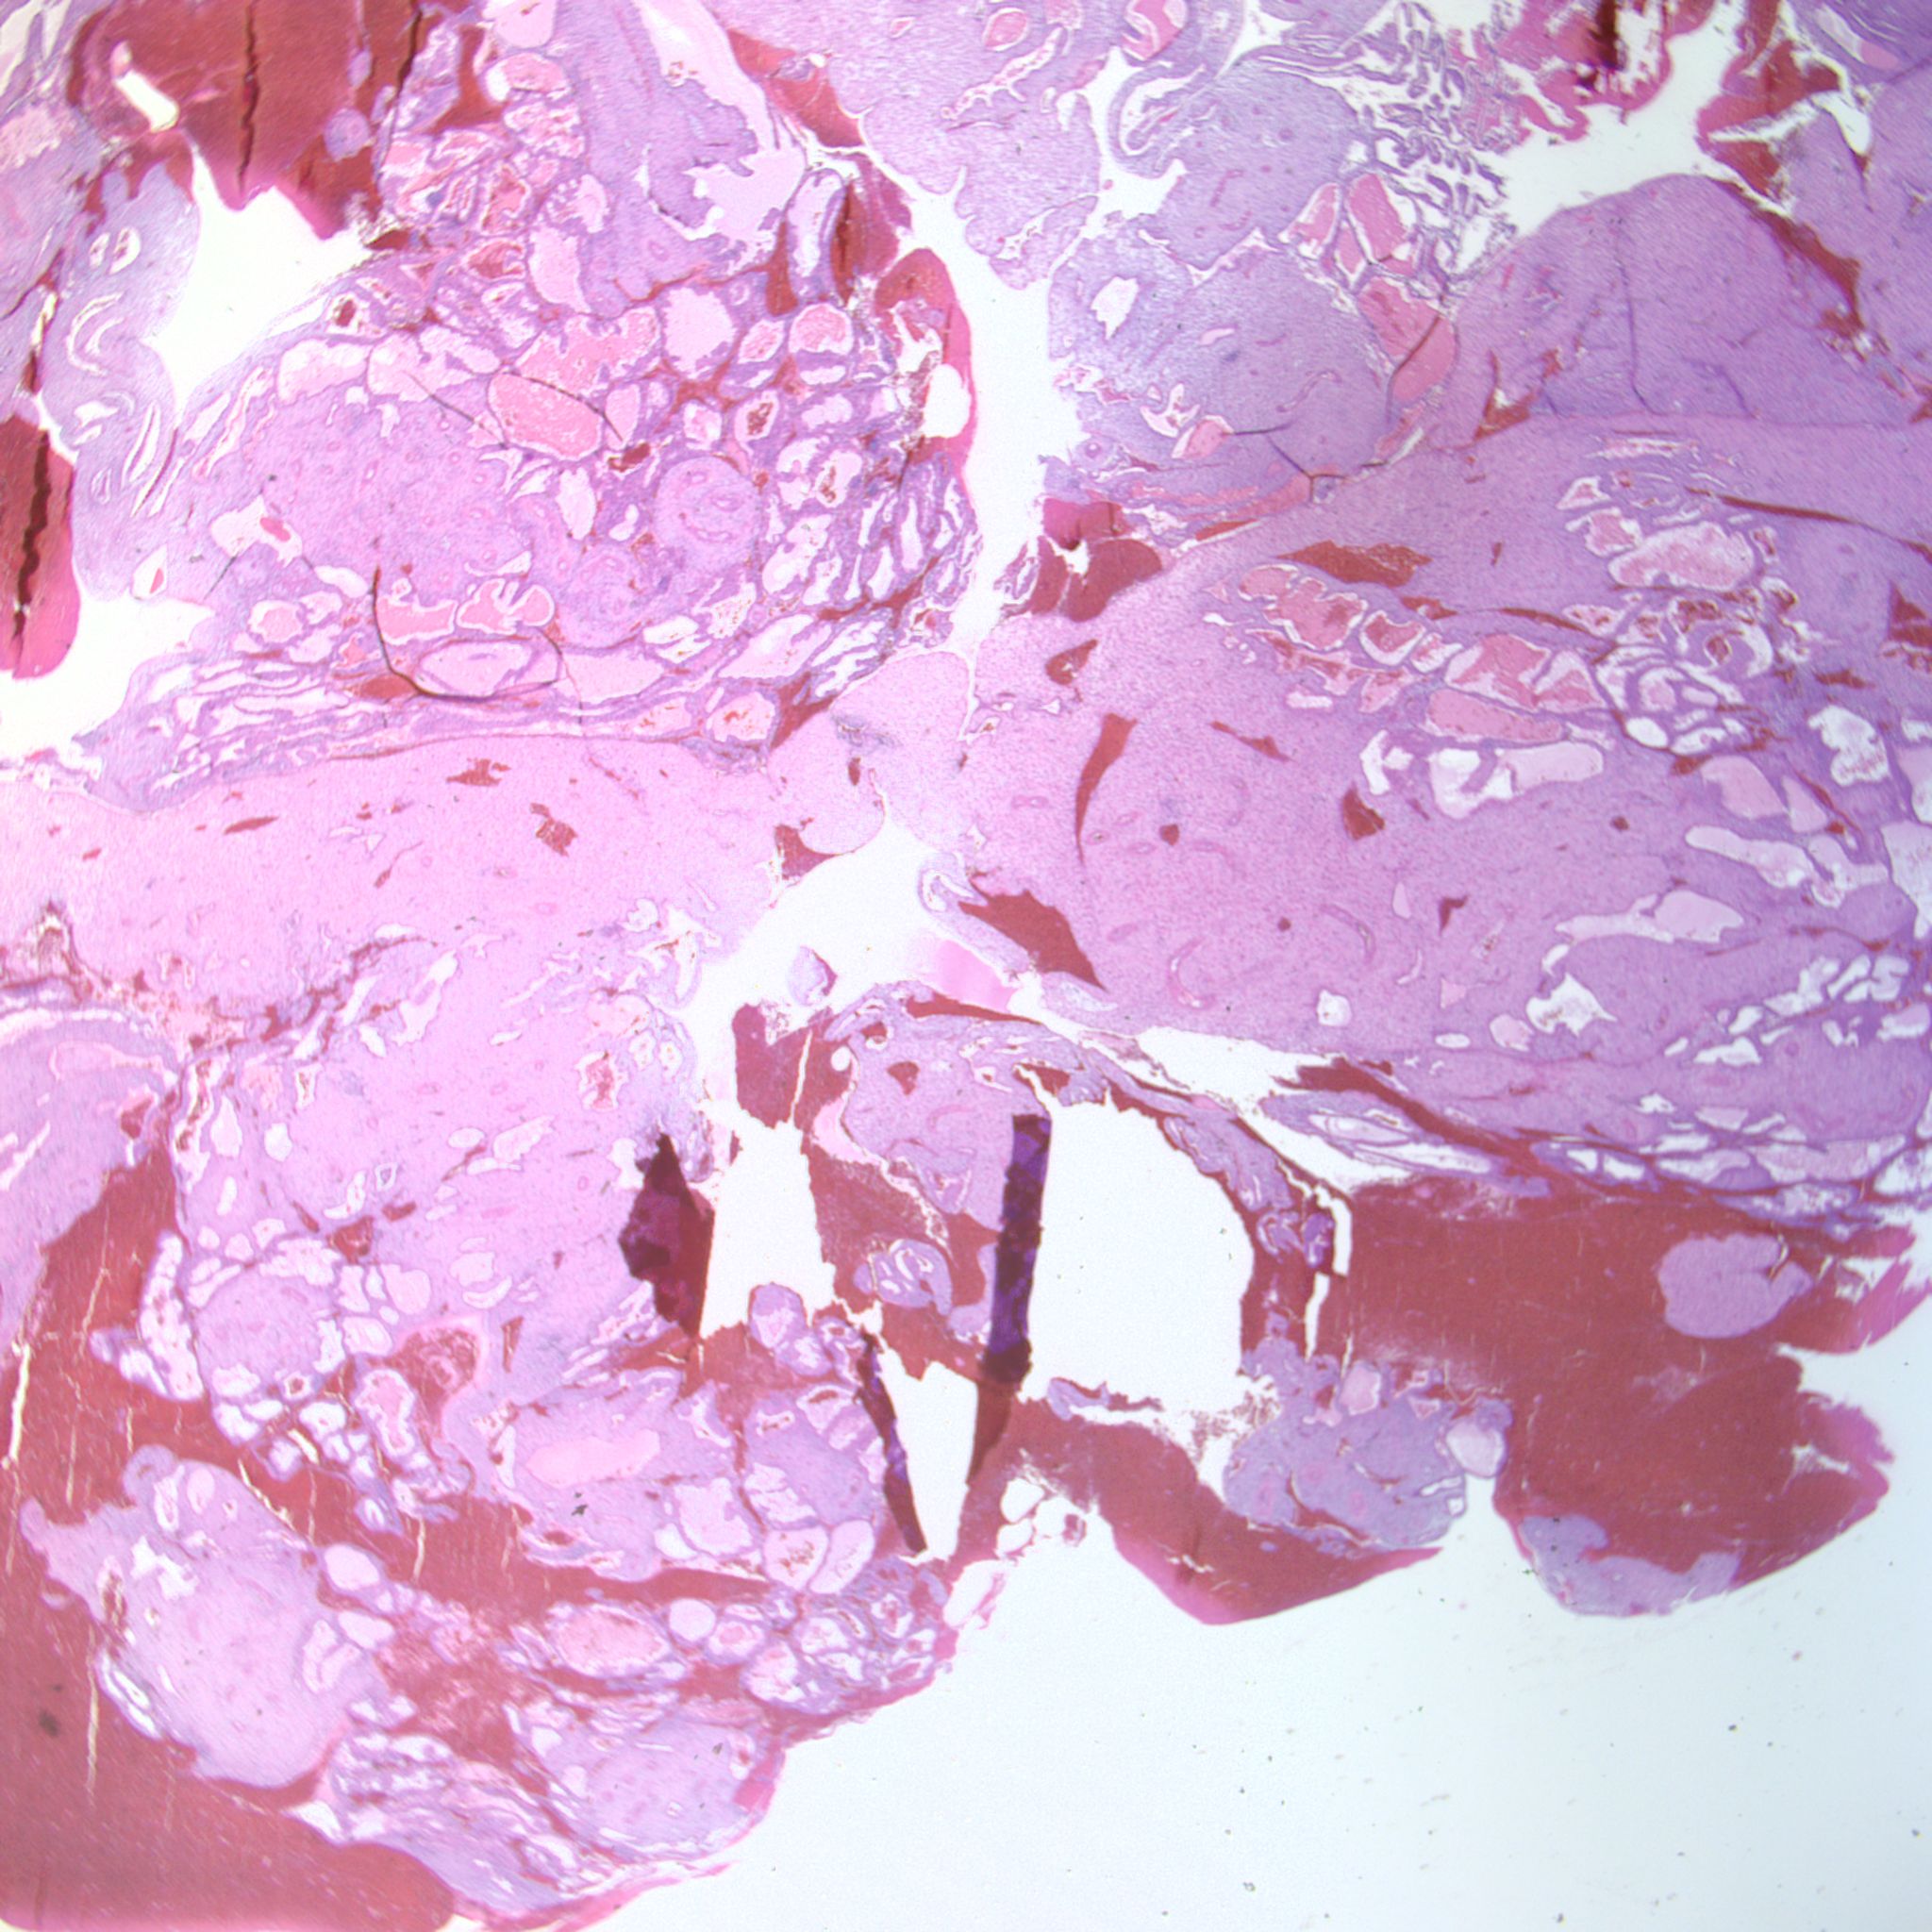

At low power we see throughout the specimen that numerous enlarged hydropic chorionic villi are present (circles).